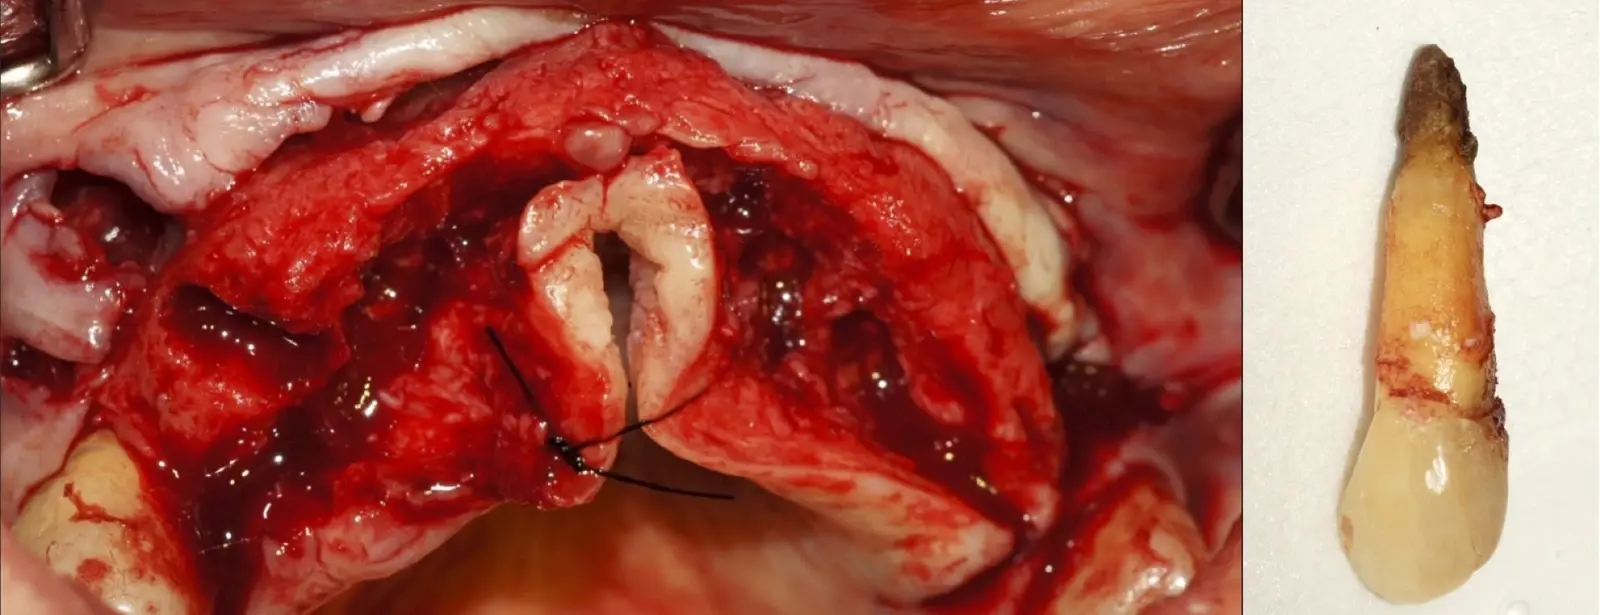

El procedimiento se inicia colocando anestesia y elevando un colgajo mucoperióstico a espesor completo y exponiendo la zona. En seguida se realiza la enucleación de la lesión, eliminando o creando una ventana en la lámina cortical que contiene el área del ápice.

El procedimiento se inicia colocando anestesia y elevando un colgajo mucoperióstico a espesor completo3 (incisión semilunar o intrasurcular con/sin protección papilar) y exponiendo la zona. En seguida se realiza la enucleación de la lesión, eliminando16 o creando una ventana17 en la lámina cortical que contiene el área del ápice; este retiro óseo se realiza con los insertos de forma aplanada dentada o inserto con cobertura diamantada plano o redondo, recordando ser lo más conservador posible (Figura 5).

Después de realizado el acceso e identificado el ápice, se procede a la limpieza de la zona con instrumentos manuales y/o con insertos diamantados de parte activa angulada para poder eliminar todo el tejido patológico del perímetro radicular apical y del tejido óseo circundante (Figura 6).